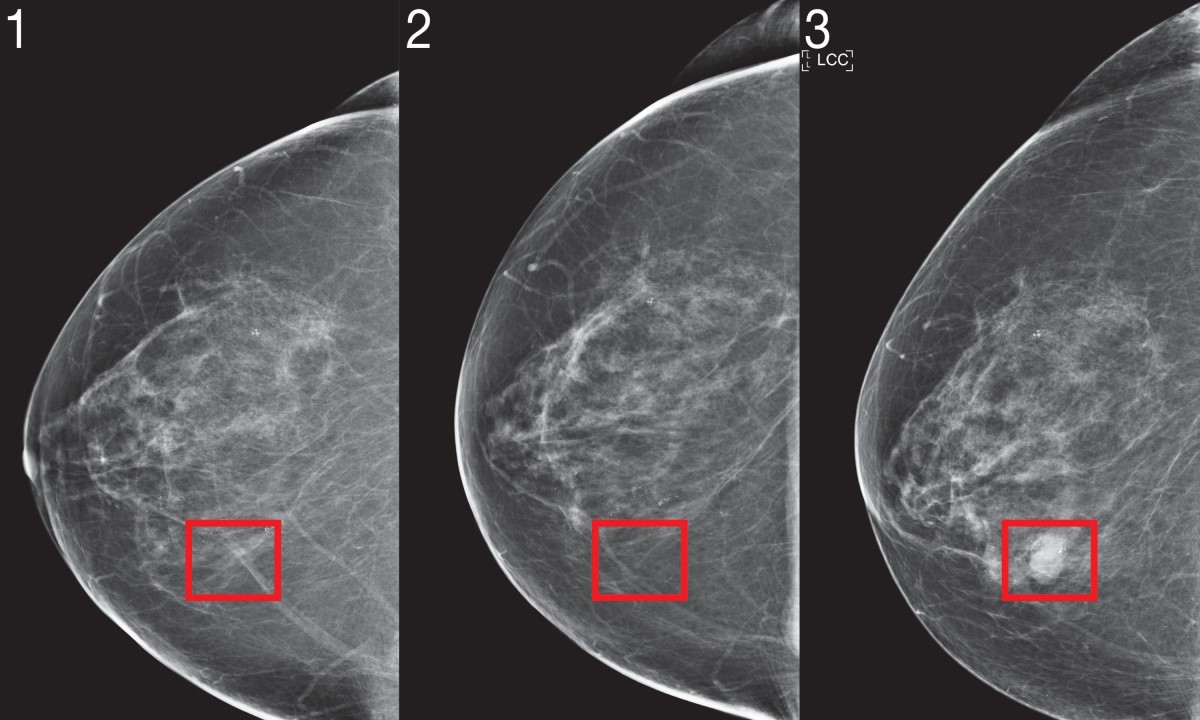

Nova umjetna inteligencija: Otkriva rak dojke godinama prije nego što se razvije

17.03.2023. | 18:28Institut za tehnologiju iz Massachusettsa (MIT) razvio je umjetnu inteligenciju (AI) koja može prepoznati potencijalni razvoj raka dojke godinama prije nego što ga je moguće otkriti mamografom. Kako t…